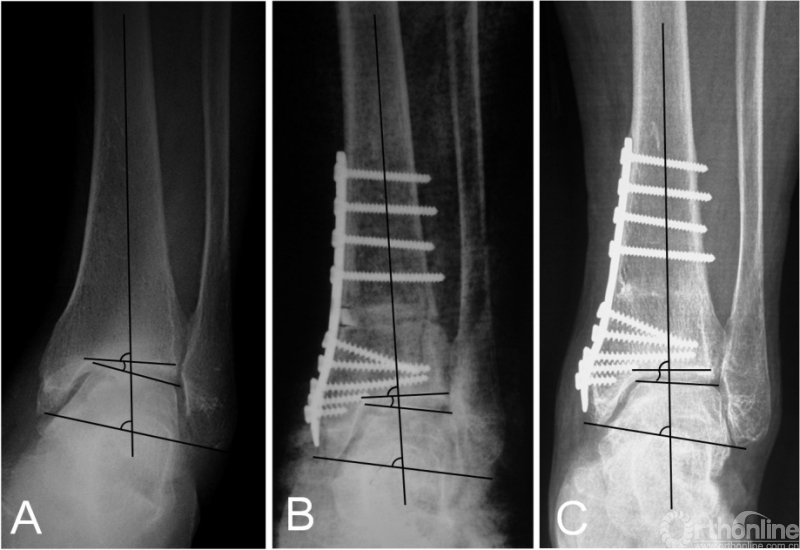

临床评估内容包括术前及末次随访的美国足踝骨科协会(American orthopedic foot and ankle society,AOFAS)踝与后足评分、Maryland足部评分踝关节骨关节炎量表(Ankle Osteoarthritis Scale,AOS)进行临床评估[25],并测量比较踝关节活动度(Range of Motion,ROM)。为了便于量化统计,将改良Takakura分期的2、3A、3B及4期分别赋值为2、3、4、5。影像学测量内容包括胫骨前侧关节面角(tibial anterior surface angle,TAS)、距骨倾斜角(talar tilt angle,TT)、胫骨踝穴角(tibiocrural,angle,TC)以及胫骨侧位关节面角(tibial lateral surface angle,TLS)(图1)。

图1 踝关节前后位X线片(1A):TAS,胫骨前侧关节面角;TT,距骨倾斜角;TC,胫骨踝穴角。踝关节侧位X线片(1B):TLS胫骨侧位关节面角。

在踝上截骨时,是否及何时需要辅助腓骨截骨目前尚无定论。在早期的报道中,腓骨截骨被要求作为常规术式来矫正踝关节内翻畸形[19-21];然而,后来的一些研究则要求在所有患者中保留腓骨[6,11,13,15]。而我们只在需要时才辅助腓骨截骨,评估内容分为术前和术中。术前评估包括:1)患侧TC角较健侧减小超过5°或存在内翻改变;2)存在腓骨骨折畸形愈合;3)患者因胫骨骨骺损伤史而导致腓骨相对较长。术中主要评估在胫骨远端关节面积距骨复位时,是否存在外侧阻挡。生物力学研究指出,在胫骨远端关节面外翻时,胫距关节的接触压强并未随之显著外移,而是在内侧形成峰值压强;只有在腓骨截骨后,胫距关节的接触压强才随着外翻角度的增大逐渐转向外侧[24]。因此,在这种情况下,腓骨截骨可以促进关节协调性的恢复,以及接触压力的外移[12]。根据我们的研究结果,腓骨截骨组的患者,TT角的改善程度更加显著(图3)。尽管两组的术后平均TT角基本一致,这正说明在腓骨截骨组,患者的术前内翻畸形更加显著。另外,我们的研究也发现腓骨截骨组的TC角改善更加明显。

图3 术前X线片提示内翻型踝关节骨关节炎(3B期),行踝上截骨合并腓骨截骨术后2年,患者的关节匹配度及负重力线均矫正良好,距骨倾斜角从术前的14.5°降至1.2°。